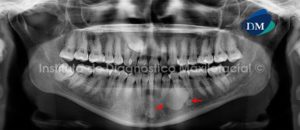

Paciente femenino de 25 años de edad que es referida por presentar la persistencia de la pieza 53 y probable ausencia de la pieza 13. A la evaluación de la radiografía panorámica se observa la retención intraósea del canino superior derecho; pero como hallazgo se evidencia una imagen radiopaca de límites parcialmente definidos, localizada en la parasínfisis mandibular del lado izquierdo, que se extiende desde la región de la pieza 33 hasta la región de la pieza 35 y que presenta además una aparente proximidad al conducto dentario inferior. Signos radiográficos compatibles con Osteoesclerosis Idiopática(Fig. 1).